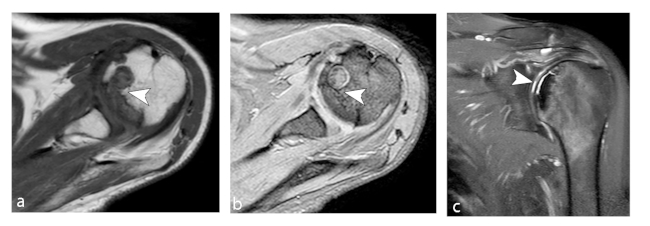

La ON de rodilla afecta a los cóndilos femorales y platillo tibial, denominándose enfermedad de Ahlback cuando se presenta de forma espontánea debido a osteoporosis e insuficiencia subcondral.11 Se presenta alrededor de los 60 años, con frecuencia en el sexo femenino en una relación 3 a 1. El cóndilo femoral interno es el sitio más frecuente afectado debido a ser un área de carga, siendo generalmente unilateral.

Está asociada al consumo de corticoides, suele ser bilateral y en pacientes más jóvenes.5 La afectación de las mesetas tibiales es poco frecuente.

Los primeros estadios de la lesión se caracterizan por una fractura subcondral sin asociación de hallazgos osteonecróticos, reconocida en RM por una imagen lineal de baja señal ponderada en T1, subcortical, y edema periférico extenso mejor evidenciado en secuencias ponderadas en T2. Al avanzar su estadio, estas lesiones osteonecróticas muestran cambios distales por una cicatrización deficiente, lo que genera reacción y formación de cartílago con tejido fibroso indicativo de retraso o falta de unión.11

En RM en secuencia ponderada en T1, la intensidad de señal de la grasa de la médula ósea del cóndilo femoral afectado es reemplazada por un área con baja señal, asociada a una periferia de aún más baja señal (►Figs. 4 y 5).8 En la secuencia ponderada en T2 se visualiza lesión central hipointensa con área de señal alta periférica en relación al patrón de edema de la médula ósea (►Fig. 6).11